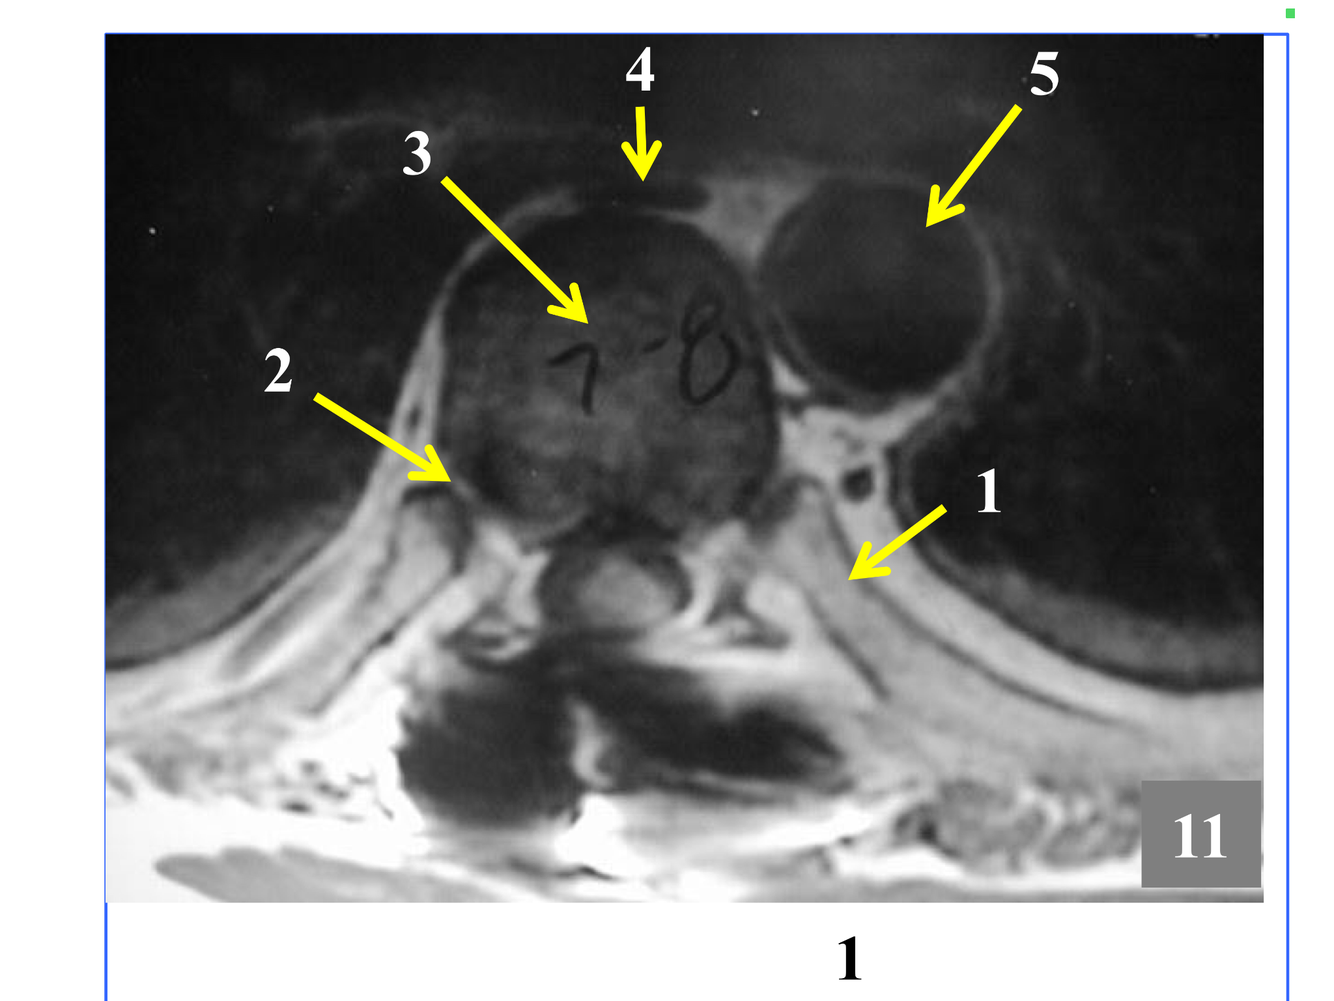

* The stack of inferior and superior articulating processes, and the zygapophyseal joints they form

*Comprised of the inferior and superior articulating processes, and the zygapophyseal joints they form

* Not seen in its entirety